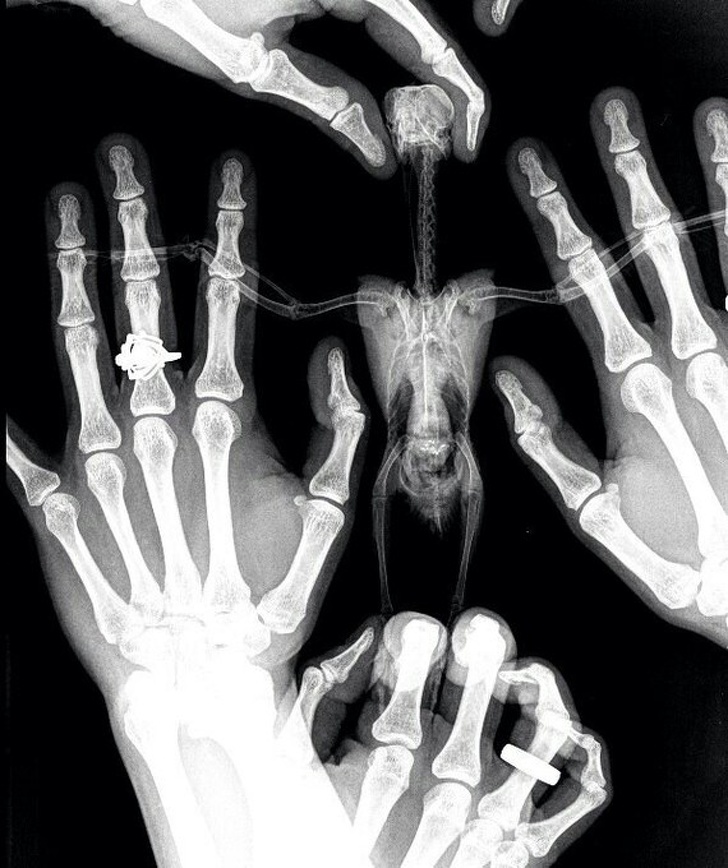

5.鸟的X射线